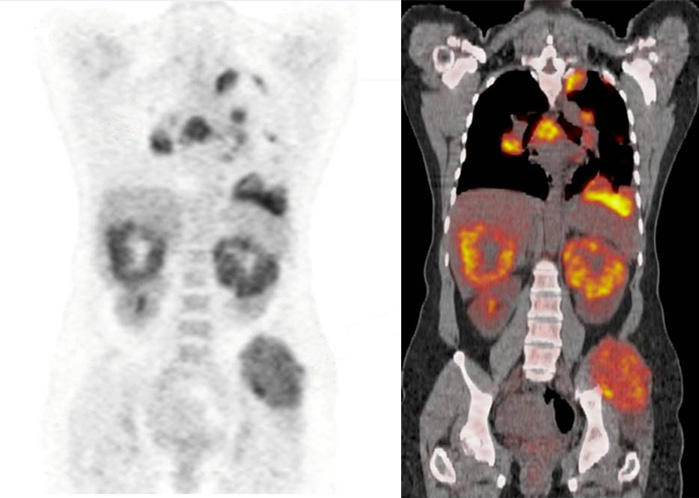

![Value of [68Ga]Ga-NYM046 PET/CT, in Comparison with 18F-FDG PET/CT, for ...](https://jnm.snmjournals.org/content/jnumed/65/12/1884/F6.large.jpg)

![Value of [68Ga]Ga-NYM046 PET/CT, in Comparison with 18F-FDG PET/CT, for ...](https://jnm.snmjournals.org/content/jnumed/65/12/1884/F5.large.jpg)